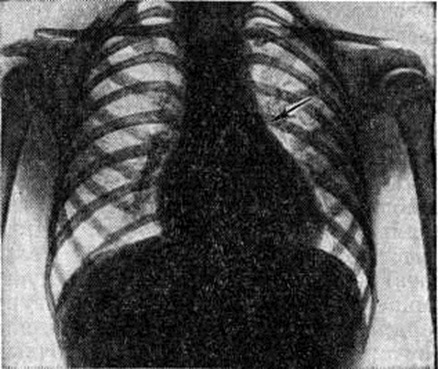

Рентгенограмма грудной клетки больного с дефектом межжелудочковой перегородки (прямая проекция): тень сердца увеличена за счёт обоих желудочков, заметное выбухание дуги лёгочного ствола (указано стрелкой), лёгочный рисунок в прикорневых отделах лёгких усилен.

При рентгенологическое исследовании у больных со средними и большими дефектами перегородки находят увеличение обоих желудочков, усиление лёгочного рисунка в прикорневых отделах лёгких и расширение тени лёгочных сосудов (рисунок 10). С развитием лёгочной гипертензии размеры сердца несколько сокращаются, начинает выбухать дуга лёгочного ствола, ослабляется периферический лёгочный рисунок, резко гипертрофирован и увеличен правый желудочек.